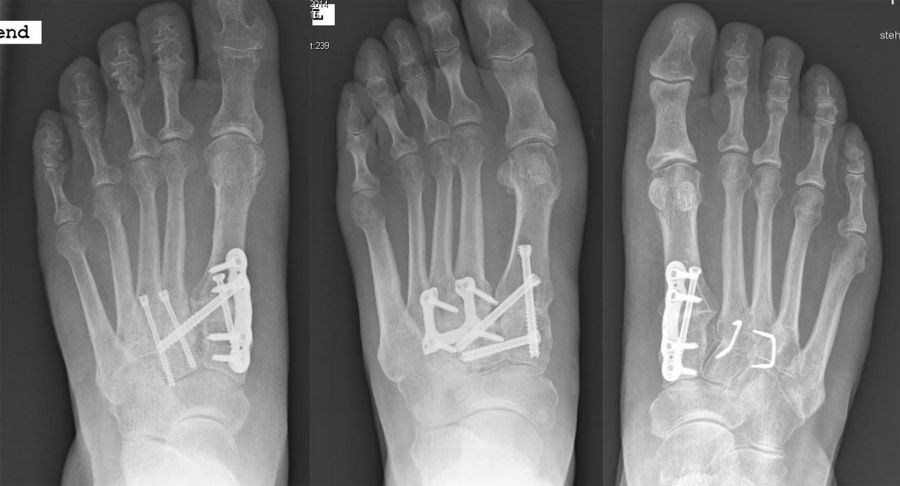

Es kommen verschiedene technische Möglichkeiten der operativen Versorgung in Frage.  Verwendung finden vor allem winkelstabile Plattensysteme, Schraubenosteosynthesen, Klammern, intraossäre Nagelsysteme, temporäre Kirschnerdraht-Transfixationen, Einbolzen von trikortikalem Span und Anlagerung von Spongiosa aus dem Beckenkamm oder dem Tibiakopf  (Abb. 2 und 3).

Durch die Arthrodese soll, wie oben beschrieben, eine Schmerzreduktion, eine Wiederherstellung der Fußstabilität und eine Korrektur der Fußstellung erreicht werden. Hierbei gibt es unterschiedliche Ansätze. Einige Autoren versteifen stets die mediale und laterale Säule bei TMT-Arthrosen 22. Andere Autoren sind der Meinung, dass nur die mediale Säule versteift werden sollte 18. Andere wiederum dehnen den Eingriff aus und beziehen die Cuneiforme-Gelenke mit in die Lisfranc-Arthrodese ein 21. Grundsätzlich zeigt sich der Trend, dass nur isoliert die arthrotischen und symptomatischen Gelenke versteift werden, ferner die Zugangswege klein und die Resektionsflächen der einzelnen Gelenke nur bis zur subchondralen Spongiosa eröffnet werden 23.

Die isolierte Arthrose der Bona Jäger Gelenkreihe (navikulocuneiforme Gelenk) ist selten und oft posttraumatisch. Meistens geht die navikulocuneiforme Arthrose mit einem schmerzhaften Pes planovalgus einher 2425. Letztlich werden die betroffenen Gelenkflächen angefrischt und mittels verschiedener Implantat-Möglichkeiten (s.o.) fusioniert. Bei gleichzeitiger Plattfußfehlstellung sollte diese ebenfalls adressiert werden 26 (Abb. 4). Ziel ist die Arthrodese in anatomischer Stellung der Gelenke.